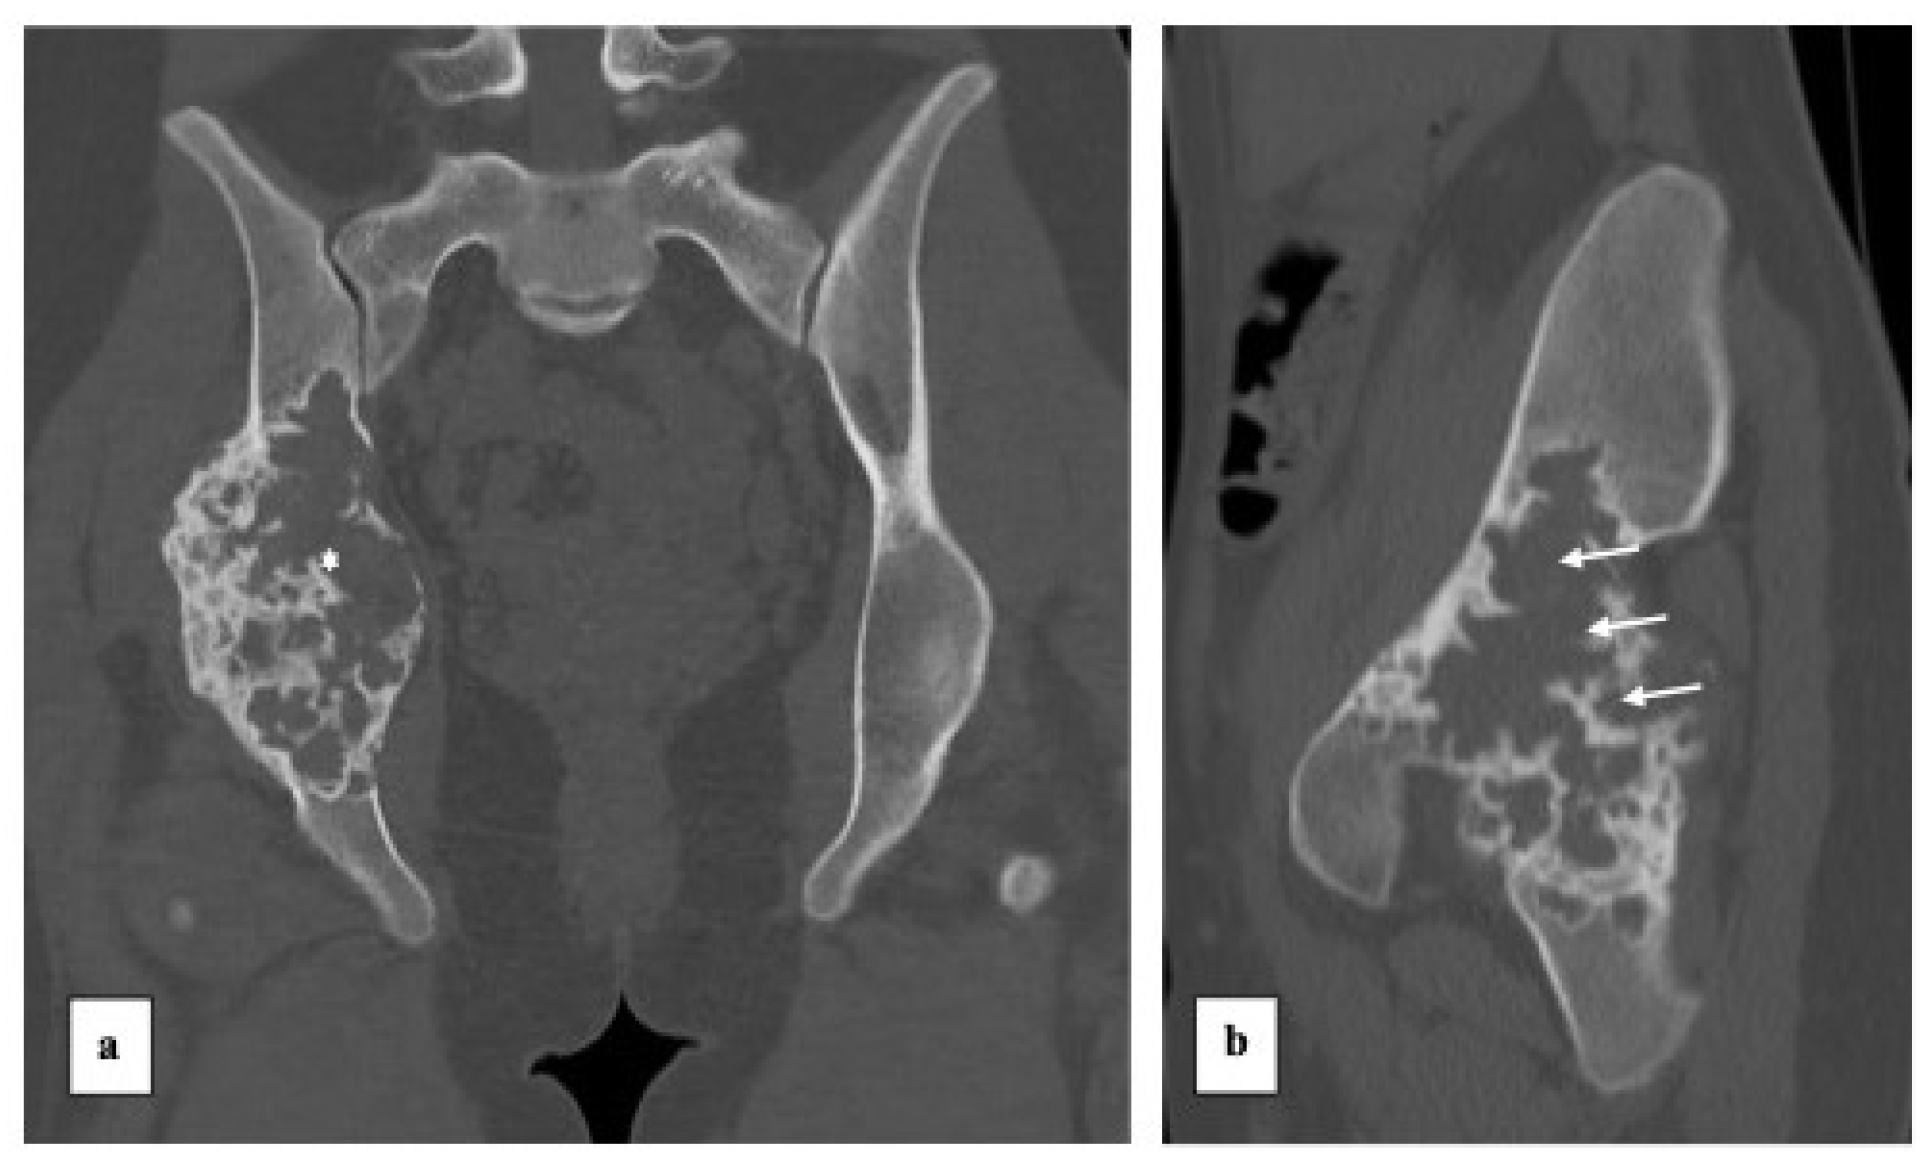

Custom-Made 3D-Printed Prosthesis after Resection of a Voluminous Giant Cell Tumour Recurrence in Pelvis

2. Case Presentation